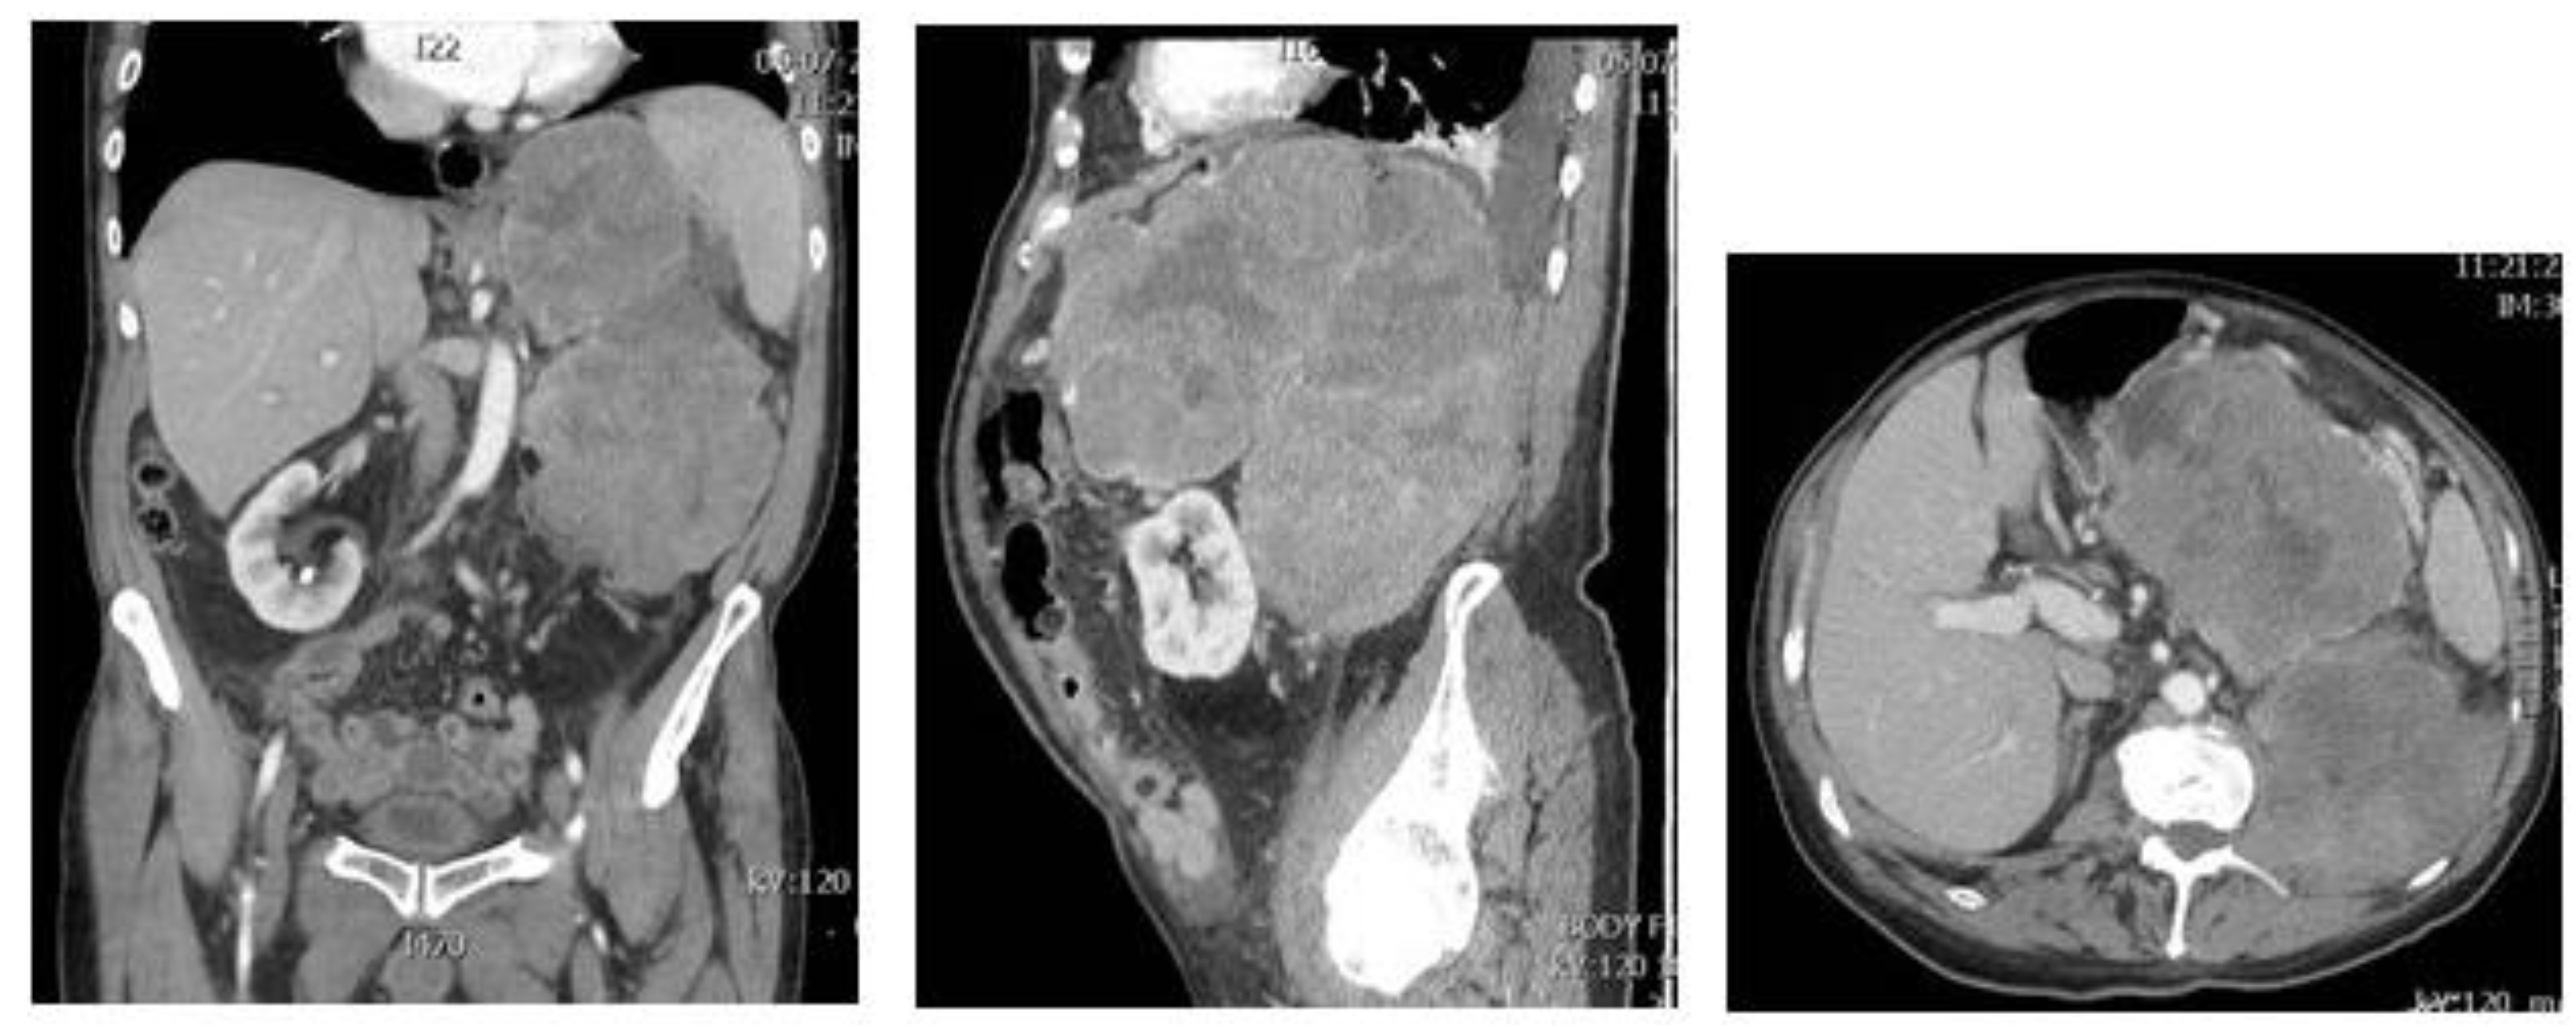

3. Dedifferentiated Liposarcoma

4. Intimal Sarcoma

- Dei Tos, A.P.; Marino-Enriquez, A.; Pedeutour, F. Dedifferentiated liposarcoma. In WHO Classification of Tumours Editorial Board. Soft Tissue and Bone Tumors; International Agency for Research on Cancer: Lyon, France, 2020; pp. 39–41. [Google Scholar]